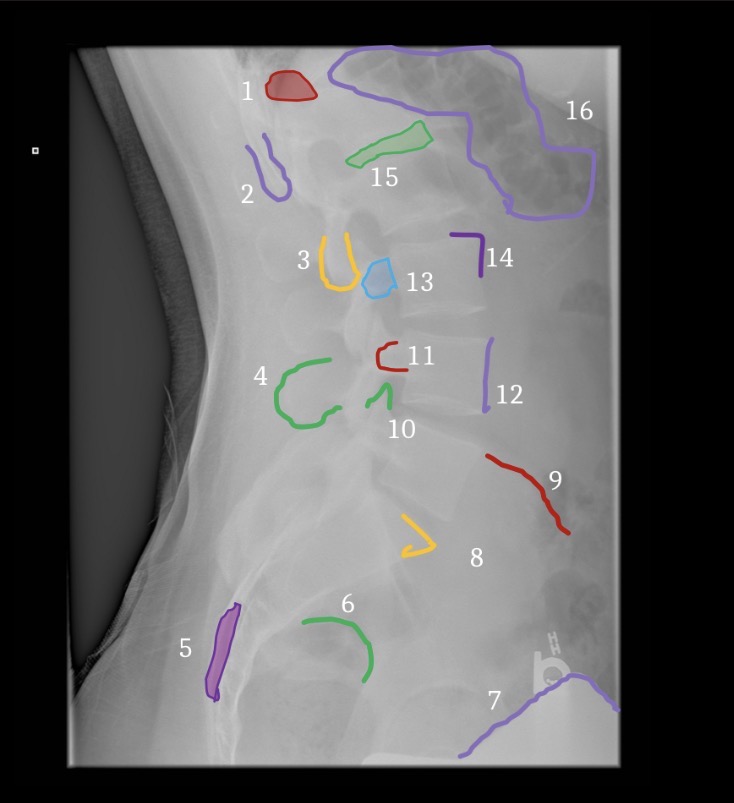

1

Brest

3

Fat deep to abdominal muscle

5

Gluteal crease

6

Lateral margin left psoas muscle

7

Hemidiaphragm

8

Gastric air bubble